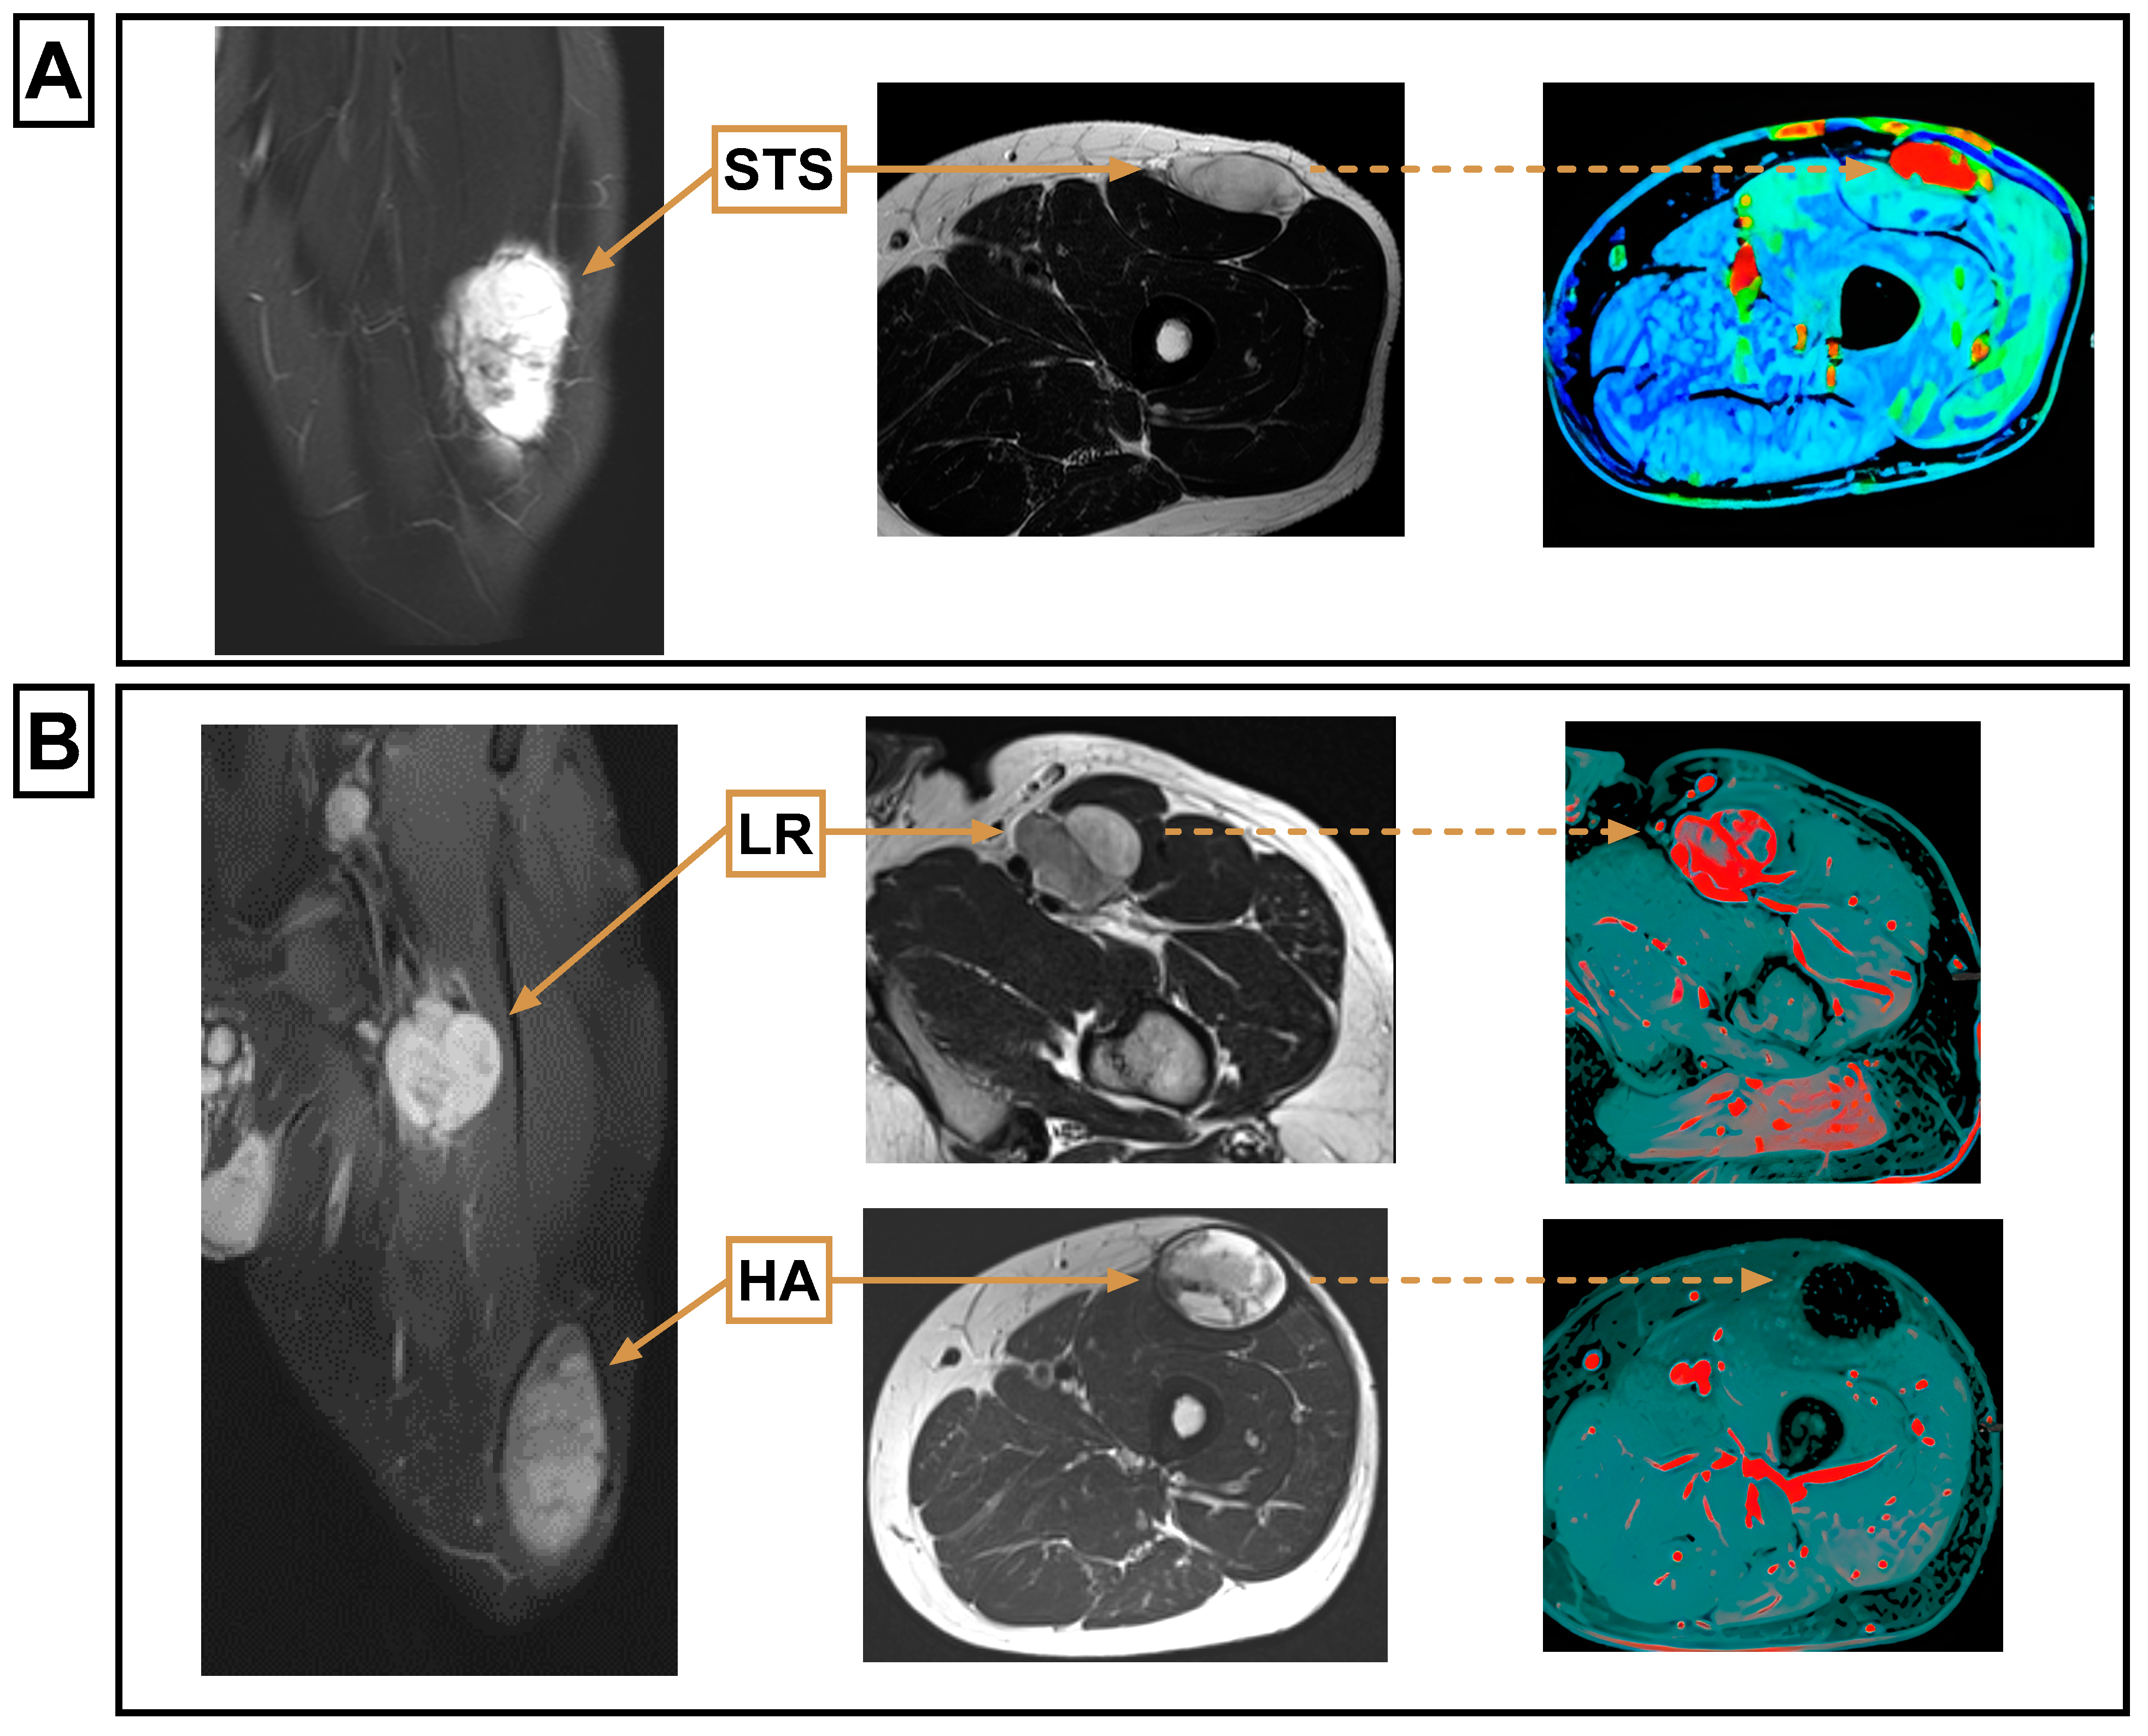

All LRs (26/26) that could be compared with the primary STS showed a matching MR morphology regarding the T1-weighted signal intensity, T2-weighted signal intensity, homogeneity, and contrast enhancement. Detailed results are provided in Table 3. Imaging examples are provided in Figure 4.

Figure 4.

Histologically verified STS showing the same T1-weighted (w) signal intensity, T2-weighted signal intensity, homogeneity, and contrast enhancement as the histologically verified LR that occurred during the course of the disease. Using these four features allows MR tomographic differentiation of LR and PTC. A newly occurring hematoma can be distinguished from an LR on the basis of the different contrast agent uptake and on the basis of the different homogeneity. (A) STS, from left to right: HASTE coronal, T2w axial, KM flooding of the primary tumor; (B) LR and HA, from left to right: T1 fat suppression post contrast coronal, upper row: LR: T2w axial, subtraction of the LR; lower row: T2w axial, subtraction of the HA. HA, hematoma; LR, local recurrence; STS, soft tissue sarcoma.